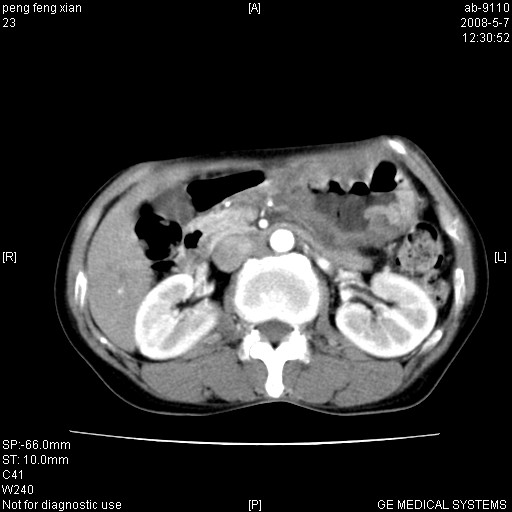

女,56岁。b超左一腹包块,考虑胃肠道肿瘤。

胃底占位待出;右肾结石?

胃体部胃壁增厚,不均匀性强化,与胰腺分解欠情.

考虑:胃癌,胰腺受侵待除外.